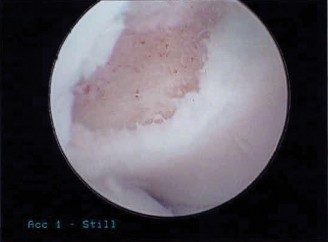

The patient undergoes conservative management consisting of rest, anti-inflammatory medications, and physical therapy. After six months, he is still not able to return to play and has progressively worsening symptoms with attempted throwing. He has a moderate elbow effusion as well as a 20-degree flexion contracture. An elbow MRI arthrogram is obtained and shown (Fig. 2–112). He elects to proceed with elbow arthroscopy. Intraoperative arthroscopic images are shown (Figs. 2–113 and 2–114).

Figure 2–112

Figure 2–113

Figure 2–114